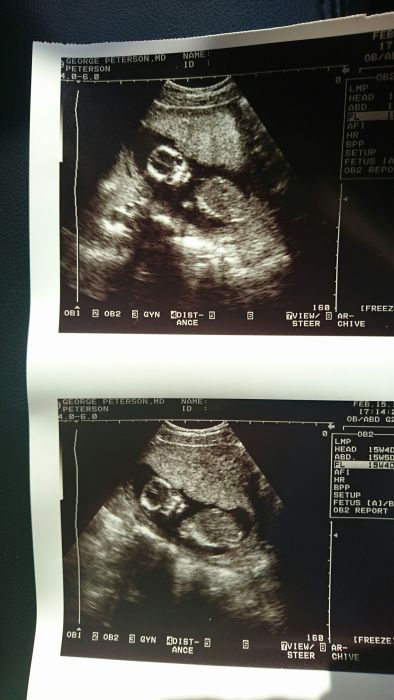

Přikládám fotku našeho ufonka. Pohlaví nám doktor řekne až na další kontrole